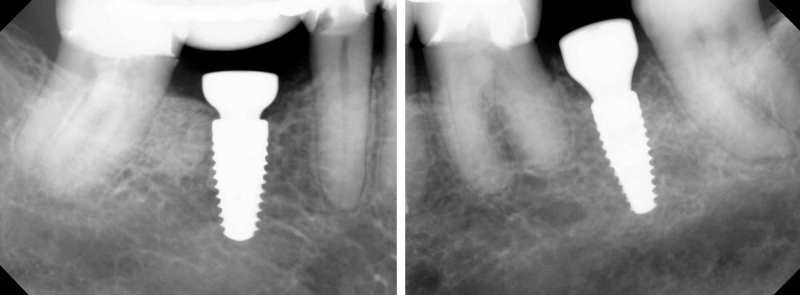

Creating the Optimal Implant Placement and Angulation

Determining the optimal implant crown placement and angulation can provide the next set of challenges. The more optimal the implant placement and angulation, the fewer insertion challenges. The implant angle relative to the adjacent interdental tooth contours must be considered. Too often, the implant is surgically angulated strictly by evaluation of the adjacent roots rather than considering the angulation of the interproximal tooth surfaces. If the implant is placed off-angle, changing from a straight to an angulated screw access may not solve the insertion path problem.

Most implant abutments extend into the head of the implant by several millimeters to take advantage of the Morris taper and engage in the timing of the “hex”. This insertion angle will dictate whether the interproximal surfaces of the restoration can pass by the interproximal surfaces of the adjacent teeth.